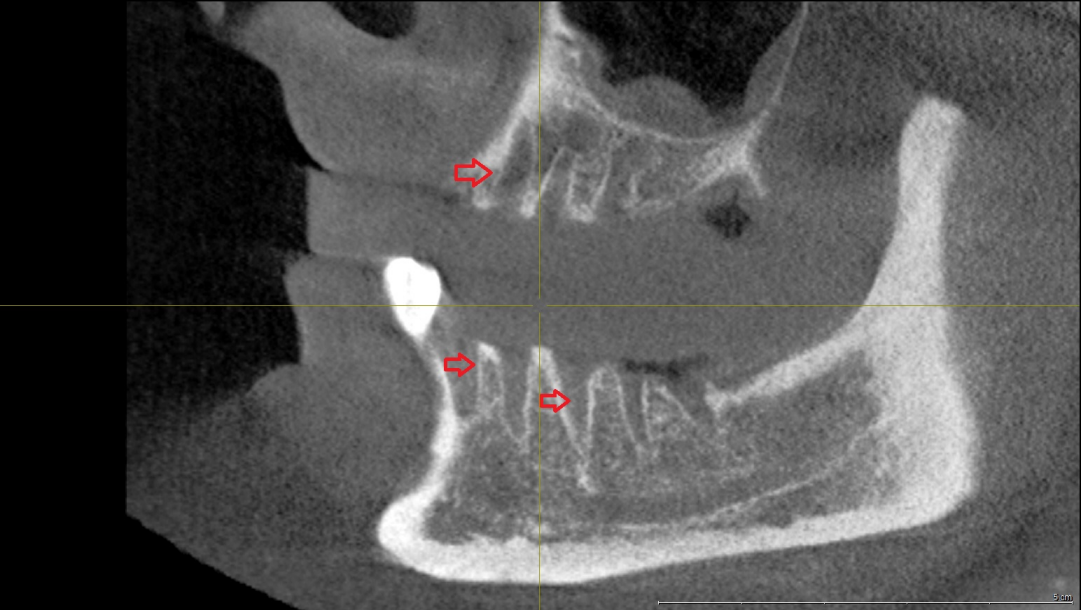

The clinical and radiographic examination revealed mandibular osteonecrosis and the patient underwent surgery under general anesthesia. This involved partial decortication of the infected maxilla and mandible (the residual anterior-posterior alveolar process and the bicortical plate exposed to vital bone) with preservation of the alveolar inferior nerve and the basal cortical margin. After resection, residual infected and necrotic tissues were removed from the remaining avital bone surface by a rotating burr and diamond burr in an attempt to prevent MRONJ recurrence. The exposed alveolar inferior nerve was protected from all cutting instruments during surgery. The wound was closed after periosteal releasing incisions, to achieve a tension-free adaption of the soft tissues. As described earlier, an adjuvant cycle of antibiotics was administered and a nasogastric tube was fitted under hospitalization for 5 days. A postoperative orthopantomograph was performed in August 2017 after surgical decortication showed vital alveolar bone (Figure 5 [Fig. 5]). The sagittal view of the digital volume tomography showed persistent bony trabecular architecture without signs of osteonecrosis (Figure 6 [Fig. 6]). No neural alterations were detected on the day after surgery. Sutures were removed 2 weeks after surgery and no intraoral wound dehiscence or new bone exposure was detected.

Figure 6: Sagittal view of the digital volume tomography (performed in August 2017) after surgical decortication. Arrows show persistent bony trabecular architecture without signs of osteonecrosis. Clinically, no signs of wound dehiscence or bone exposure were detected.